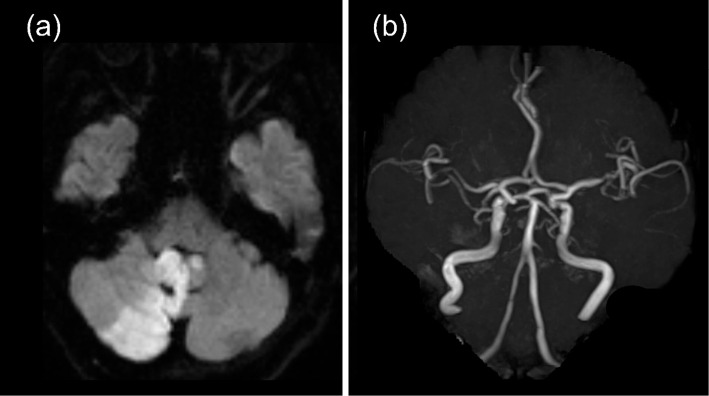

An 80-year-old woman presented with the sudden onset of vertigo and vomiting and was diagnosed with acute cerebellar infarction. Twelve days after the onset, she experienced positional vomiting, predominantly in the lying-down position, triggered by postural changes with immediate or delayed onset. Over 1 month, 23 episodes of vomiting occurred. Brain computed tomography revealed edema in the infarcted area, fourth ventricular outlet compression, and lateral ventricular enlargement. These findings suggest that fluctuations in intracranial pressure are associated with intermittent obstructive hydrocephalus exacerbated by the patient's posture. This case highlights the importance of considering postural triggers in patients with recurrent vomiting associated with cerebellar infarctions.

一位80岁的妇女表现为突然发作的眩晕和呕吐,并被诊断为急性小脑梗死。发病12天后,患者出现体位性呕吐,主要发生在平卧位,由体位变化引发,即刻或延迟发作。1个月内,呕吐发作23次。脑ct显示梗死区水肿,第四脑室出口受压,侧脑室增大。这些发现表明,颅内压波动与间歇性阻塞性脑积水有关,患者的姿势加剧了脑积水。本病例强调了考虑小脑梗死患者复发性呕吐的体位触发因素的重要性。